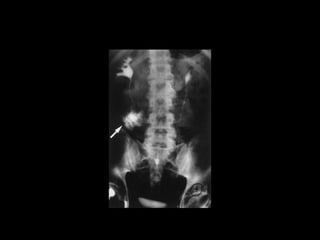

Diagnostico

• Estudio elección: cistograma de llenado 350-

400ml solución salina, con 4% de contraste a

una altura de infusión de 40 cm.

• Cystography: Gold standard

• CT Cystography : New trend